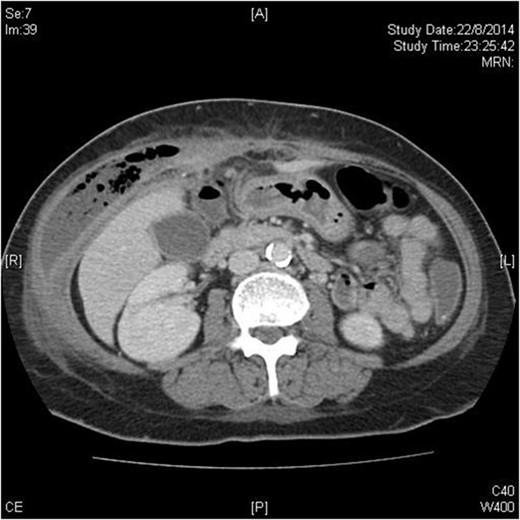

Chest X-ray showed no pneumoperitoneum. Blood tests revealed leucocytosis. A contrast computed tomography (CT) scan showed a gas-containing collection at the right abdominal wall with a linear hyperdensity visible in the abdomen (Fig. 1). There was no pneumoperitoneum nor obvious intra-abdominal organ injury.

Transverse plane of CT scan showing right-sided abdominal wall collection with fish bone just visible as a hyperdense dot just anterior to the liver.